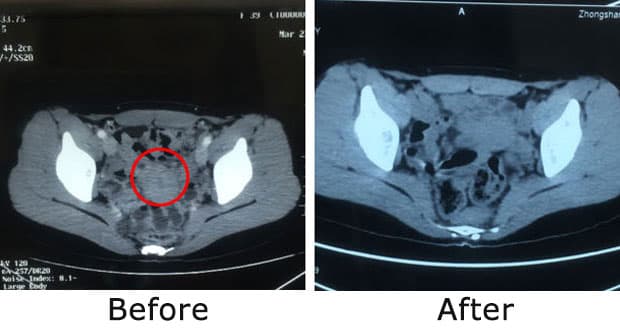

Bibi Wu,

kanker serviks stadium IVA — telah bertahan 1 tahun

Bibi Wu berasal dari Indonesia. Desember tahun lalu, beliau mengalami perdarahan vagina yang tidak teratur serta sering buang air kecil. Setelah diperiksa, ia didiagnosis menderita karsinoma sel skuamosa serviks stadium IVA. Tumor di leher rahimnya telah menyebar ke parametrium, rahim, vagina, hingga kandung kemih. Kondisi tersebut juga menyebabkan hidronefrosis yang mengganggu fungsi urinasi.

Sebelum pengobatan VS setelah pengobatan

Kemudian, beliau datang ke Modern Cancer Hospital Guangzhou untuk mendapatkan pengobatan. Selama masa pengobatan, Bibi Wu mengikuti semua arahan dokter dengan sangat baik. Setelah dua kali pengobatan embolisasi, gejala perdarahan maupun buang air kecil menunjukkan perbaikan yang signifikan. Pada kunjungan ketiga untuk kontrol ulang, hasil CT scan menunjukkan bahwa sejak pertama kali masuk hingga saat ini, ukurannya sudah mengecil hingga 80% (ukuran tumor sebelum pengobatan: 3.6 × 3.7 × 3.5 cm) dengan hasil yang sangat baik hanya dalam waktu 2 bulan, kondisi Bibi Wu kini jauh lebih stabil.